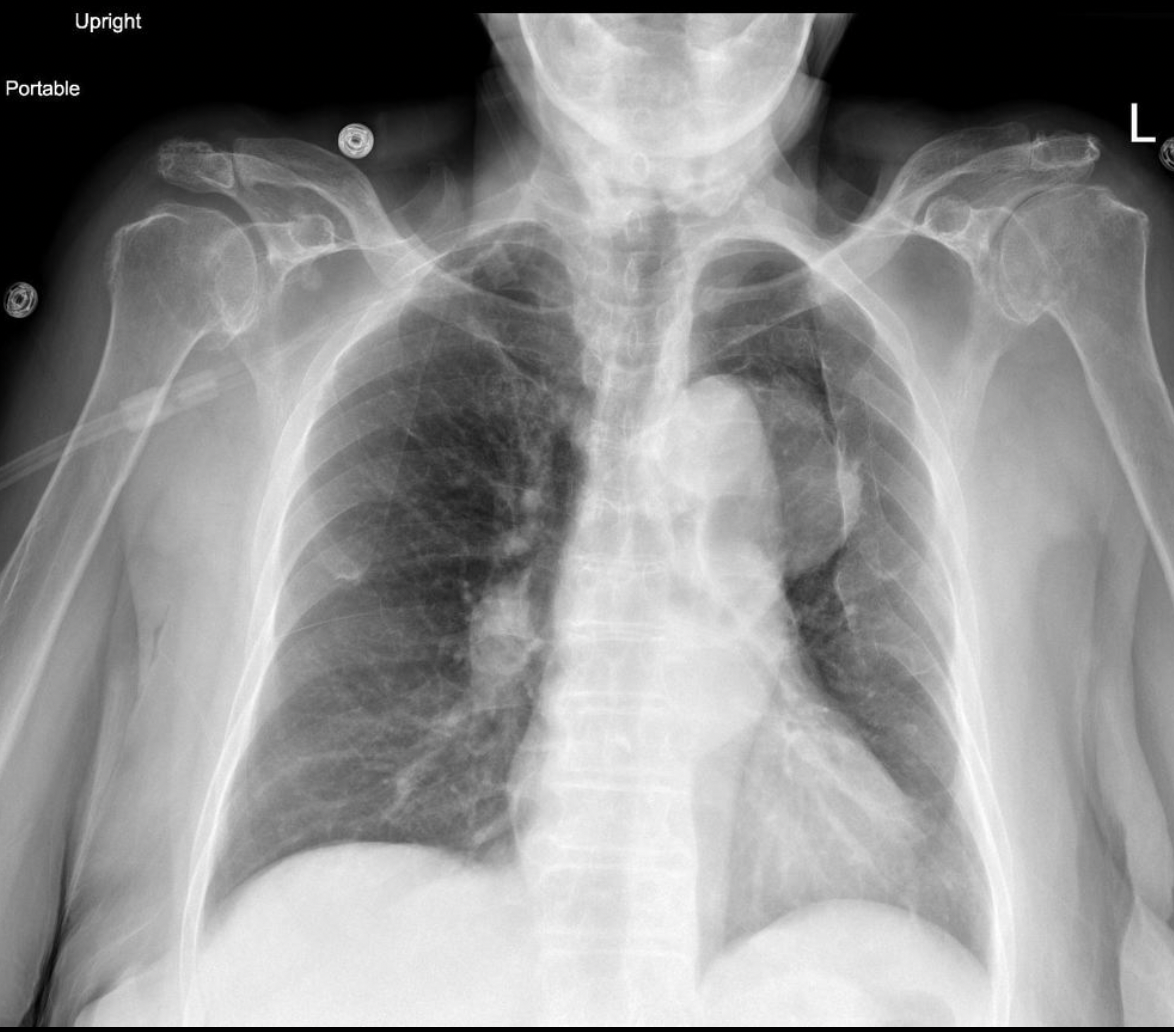

-Type A Aortic Dissection

Aortic Dissection: (Calcium sign, Enlarged Aortic Knob, Wide Mediastinum > 8cm)